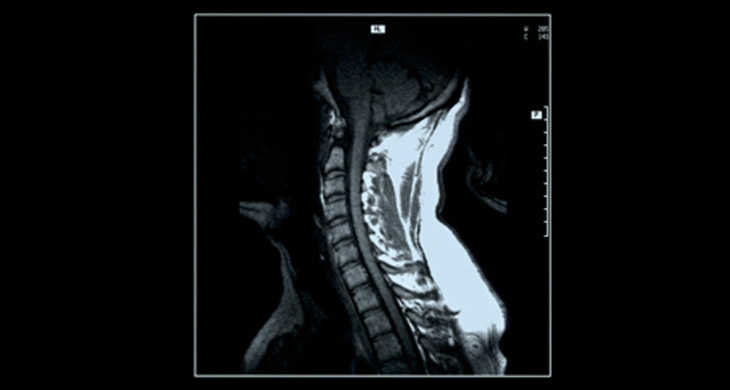

腰痛、肩こり、不眠症の方へ、大阪 睡眠改善研究室のオーダーメイド枕

(*)実際のMRI画像と異なります。

頸椎椎間板ヘルニア等でオーダーメイド枕をお探しの方へ。

睡眠改善研究室では、済生会病院と連携を取り【頸椎ドックMRI】検査をおすすめしています。

手のシビレやめまい等に繋がる頸椎椎間板ヘルニアですが、何か特別な事をしたわけでもなく気付かずになってしまう場合もあるのが特徴です。頸痛や腰痛等は運動療法や姿勢など日常生活上の注意によって緩和することがありますが、椎間板ヘルニアなど脊椎の軟骨が変性し症状を出している場合は原因を見極め正しく対処する事も大切です。

睡眠中は基本的に無意識状態になりますので、睡眠中(主に)頚椎から後頭部にかけての負担を軽減させ、睡眠姿勢を安定させる為にオーダーメイド枕が効果的になりますが、同時に【頚椎ドックMRI】などで椎間板・椎骨そのものの状態を確認するのも、原因対処に効果的になりますので、大阪 睡眠改善研究室では済生会病院と連携をとり検査をお勧めしています。